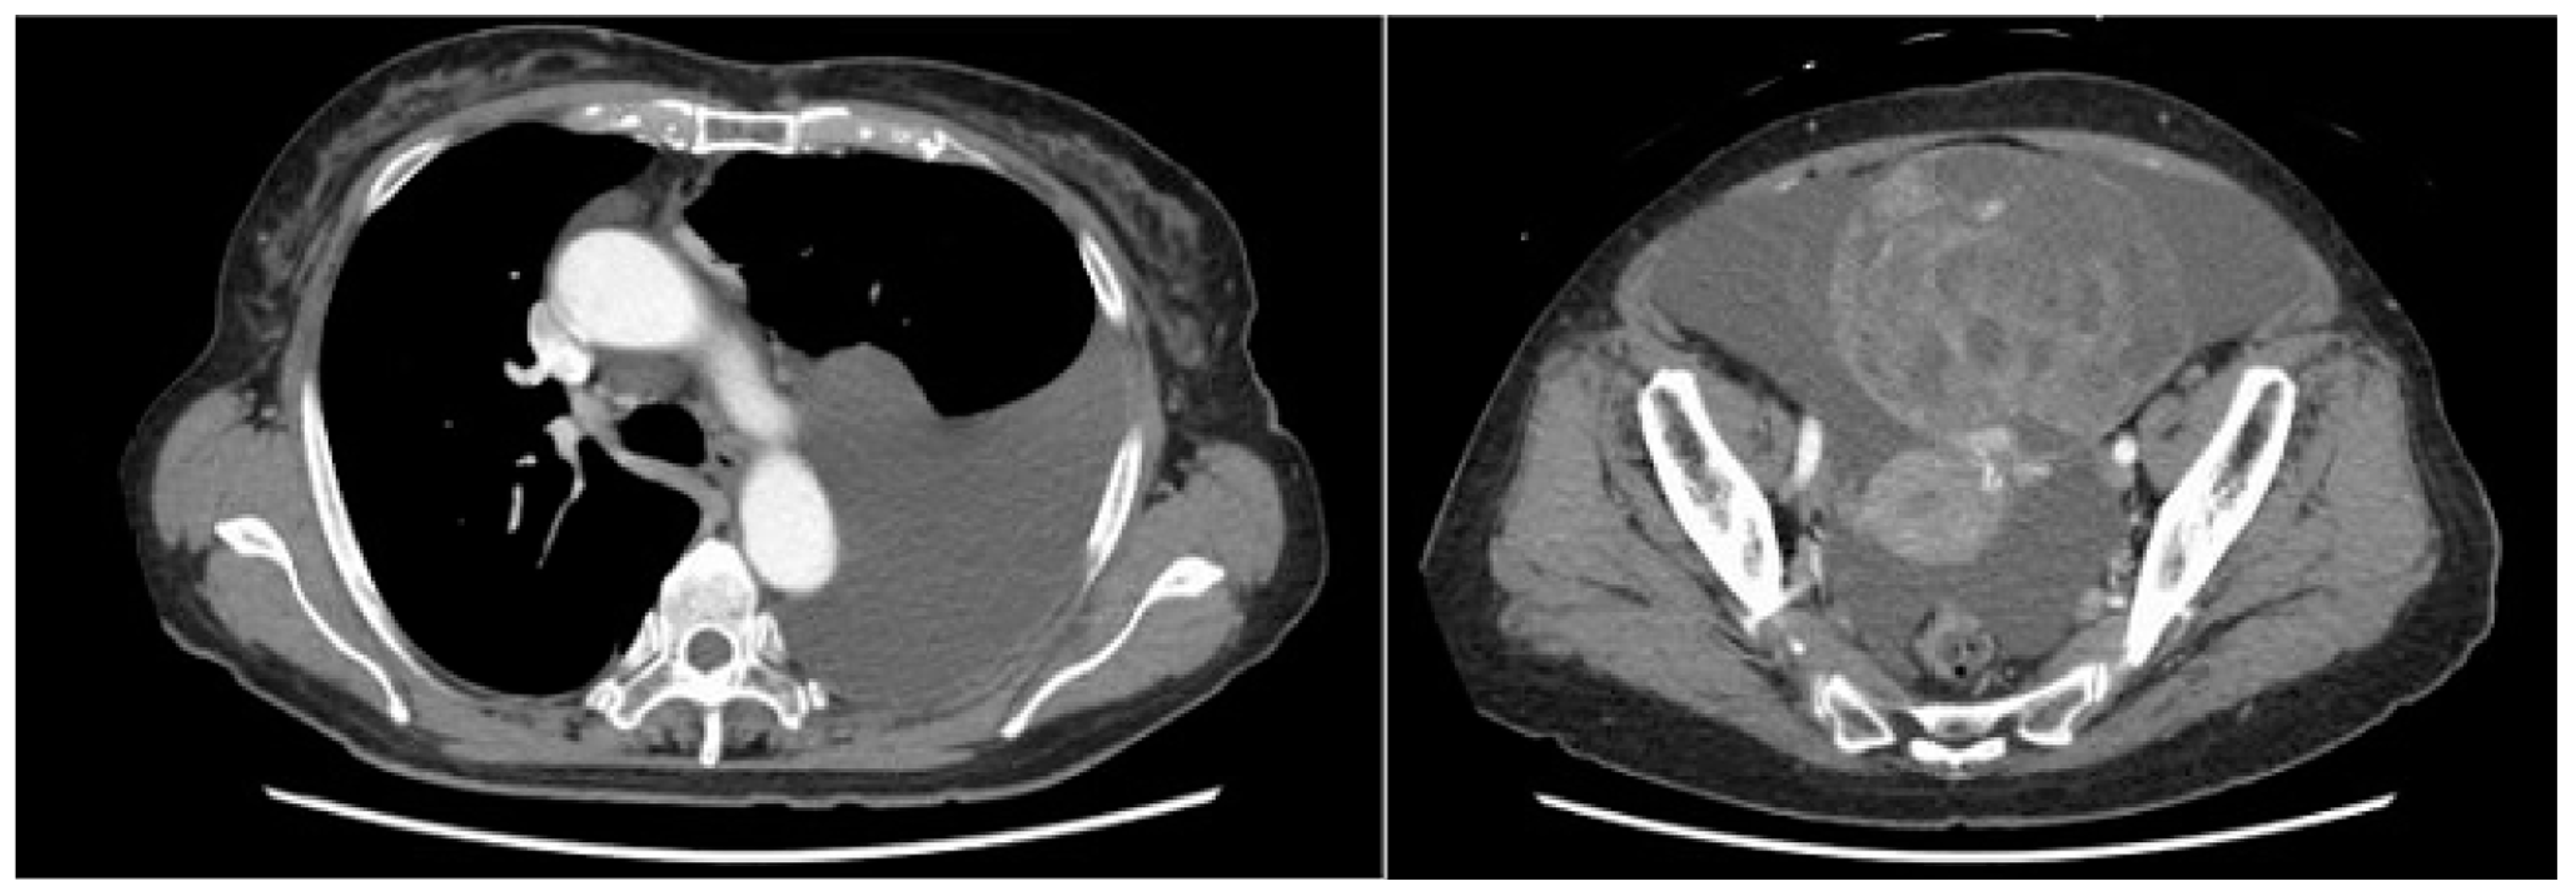

A computed tomography (CT) scan performed for close examination of abdominal distention revealed pleural and ascites effusions, which led to suspicion of a neoplastic lesion arising from the ovaries (Figure 1).

Figure 1.

Retention of pleural and ascitic fluid was observed.